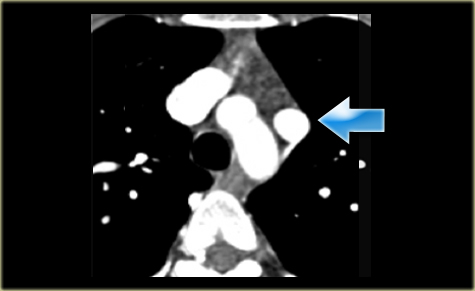

Right Arch with Aberrant left subclavian

The Right Aortic Arch with an aberrant left subclavian is an obstructing arch anomaly.

The first branch of the aorta is the left common carotid, followed by the right subclavian artery and the left common carotid.

This also is a true ring.

The ligamentum ductus arteriosus between the arch at the level of the left subclavian artery and the left pumonary artery completes the ring.

If this ligament is very short, there will be a lot of compression.

There is a right arch and the left subclavian artery is the last branch of the aortic arch, indicating that this is an aberrant left subclavian.

Medially to the left subclavian artery we see the left common carotid, that originates from the right side and has an oblique course to the left.

The yellow arrow indicates the azygos vein.

The green arrow indicates the left superior intercostal vein, a normal variant, that we will discuss later.